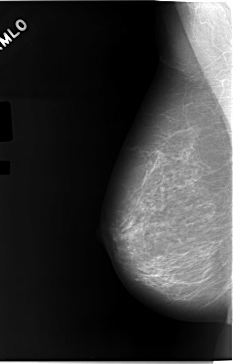

C_0046_1.RIGHT_MLO

RIGHT_MLO LINES 5824 PIXELS_PER_LINE 3720 BITS_PER_PIXEL 12 RESOLUTION 50 NON_OVERLAY